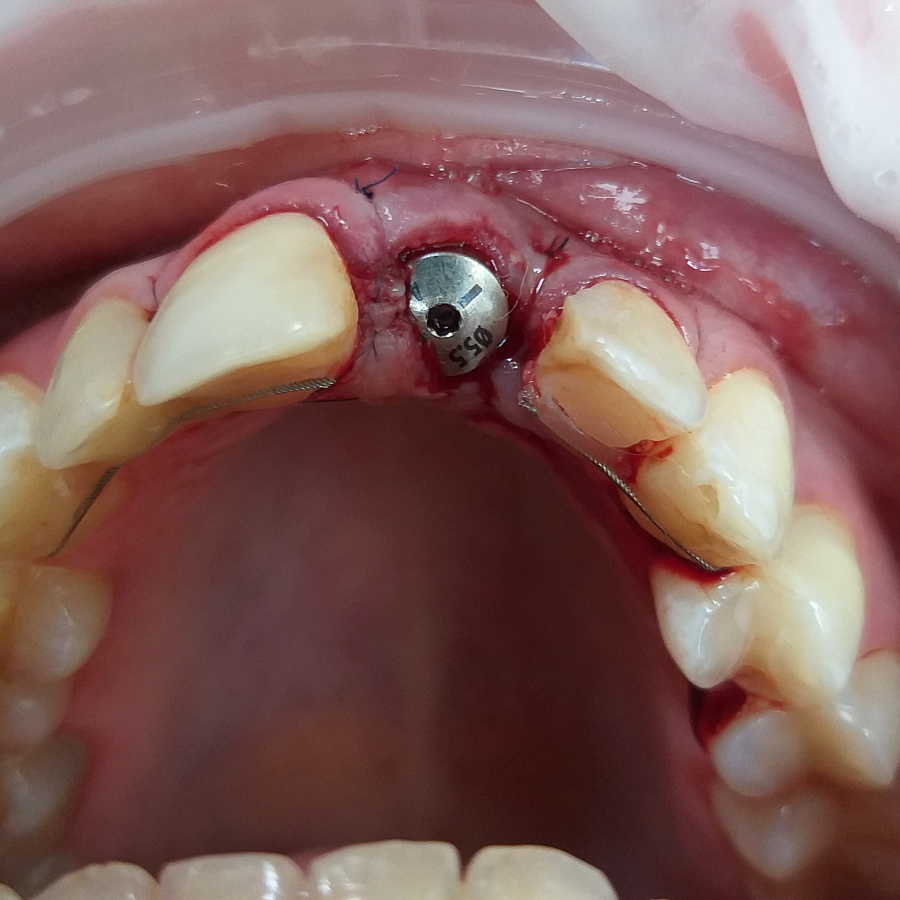

Был предложен вариант одномоментной имплантации (удаление зуба и установка импланта за одно посещение).

Следующий этап после удаления разрушенного корня и установки зубного имплантата - восстановление косметического дефекта временной коронкой, изготовленной после операции.